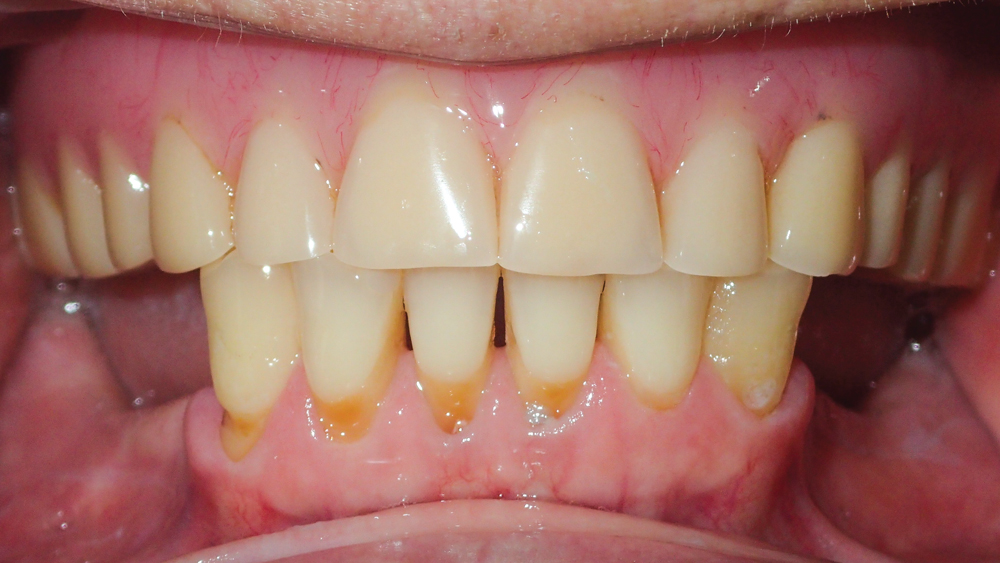

This patient was unhappy with the esthetics of her existing upper denture as well as the discomfort and instability caused by her loose-fitting mandibular partial denture. Although her concerns with the maxillary denture could be addressed with a new, more esthetic appliance, she preferred implant treatment for her mandible, where a fixed solution was needed to adequately restore function, stability and comfort.

The patient’s remaining mandibular teeth were extracted followed by immediate implant placement and delivery of a fixed provisional appliance. After integration of the implants, the prosthetic designs for the new upper denture and lower implant restoration were determined in tandem. Ultimately, the dual-arch restorations addressed the functional and esthetic challenges of the case while staying within the financial means of the patient, demonstrating the benefits of a flexible, multifaceted approach to restorative dentistry.

The dual-arch restorations addressed the functional and esthetic challenges of the case while staying within the financial means of the patient.